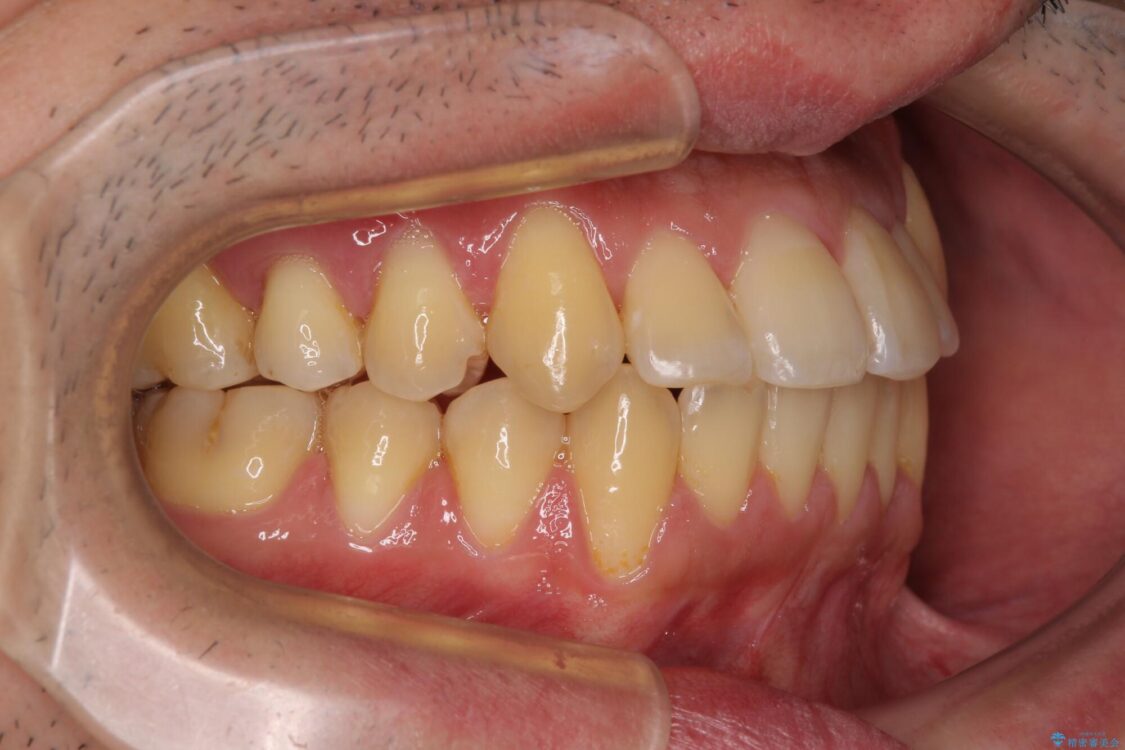

治療途中

• 八重歯とクロスバイト 目立たないワイヤー装置で矯正治療 治療途中画像